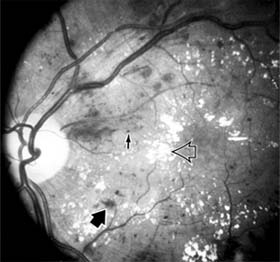

Figure 10-20

Figure 10-20: Background diabetic retinopathy with abundant macular exudate (open arrow), micro-aneurysms (small arrow), and intraretinal hemorrhage (large arrow).